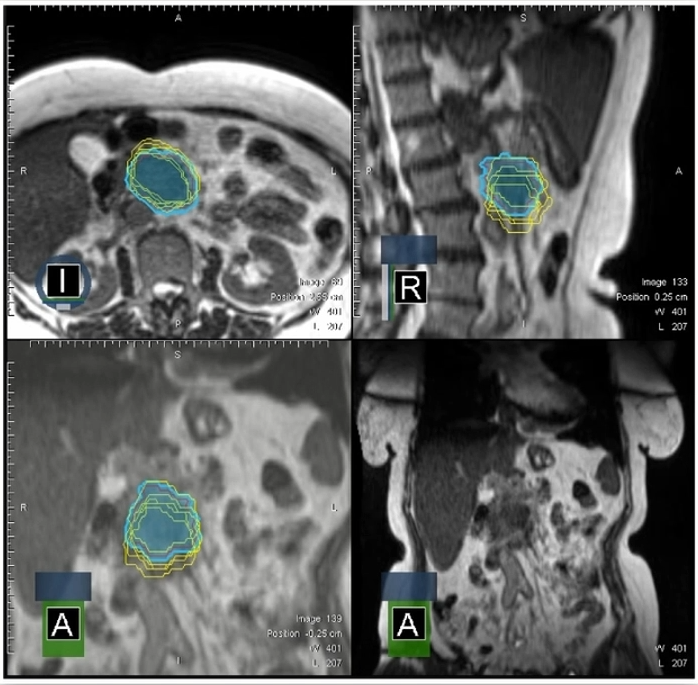

£¨2)ÔÚÿ´ÎÖÎÁÆÇ°É¨Ãè»ñµÃÇåÎúµÄMRIͼÏñ£¬£¬£¬£¬£¬£¬£¬£¬ÖØÐ¹´»­GTV²¢ÖÆ×÷ÔÚÏß×Ô˳ӦÍýÏ룬£¬£¬£¬£¬£¬£¬£¬°Ñ5¸ö·Ö´Î²î±ðµÄGTV¹´»­¾ÙÐеþ¼Ó£¬£¬£¬£¬£¬£¬£¬£¬·¢Ã÷ÔÚÒÈÏÙ°©SBRTµÄ5¸ö·Ö´ÎÖÎÁÆÊ±£¬£¬£¬£¬£¬£¬£¬£¬GTVµÄ¹´»­×ª±ä½Ï´ó¡£¡£¡£¡£¡£¡£

ͼ9 °Ñ5¸ö·Ö´Î²î±ðµÄGTV¹´»­¾ÙÐеþ¼Ó£¬£¬£¬£¬£¬£¬£¬£¬·¢Ã÷ÔÚÒÈÏÙ°©SBRTµÄ5¸ö·Ö´ÎÖÎÁÆÊ±´ú£¬£¬£¬£¬£¬£¬£¬£¬GTVµÄ¹´»­×ª±ä½Ï´ó

Dr. OzyarÌåÏÖ£¬£¬£¬£¬£¬£¬£¬£¬Í¨¹ýÔÚÿ¸ö·Ö´Î×ö¼ÁÁ¿Õ¹Íû£¬£¬£¬£¬£¬£¬£¬£¬·¢Ã÷ÈôÊÇʼÖÕʹÓÃÔ­ÍýÏëµÄ»°£¬£¬£¬£¬£¬£¬£¬£¬GTVºÍPTV»á´ó·ù¶ÈÇ·Á¿£¬£¬£¬£¬£¬£¬£¬£¬Í¨¹ýÔÚÏß×Ô˳ӦÍýÏëARTÄܾÀÕýÕâÒ»µã£¬£¬£¬£¬£¬£¬£¬£¬Èçͼ10Ëùʾ¡£¡£¡£¡£¡£¡£

ͼ 10?ͨ¹ýÔÚÿ¸ö·Ö´Î×ö¼ÁÁ¿Õ¹Íû£¬£¬£¬£¬£¬£¬£¬£¬·¢Ã÷ÈôÊÇʼÖÕʹÓÃÔ­ÍýÏëµÄ»°£¬£¬£¬£¬£¬£¬£¬£¬GTVºÍPTV»á´ó·ù¶ÈÇ·Á¿£¬£¬£¬£¬£¬£¬£¬£¬Í¨¹ýÔÚÏß×Ô˳ӦÍýÏëARTÄܾÀÕýÕâÒ»µã